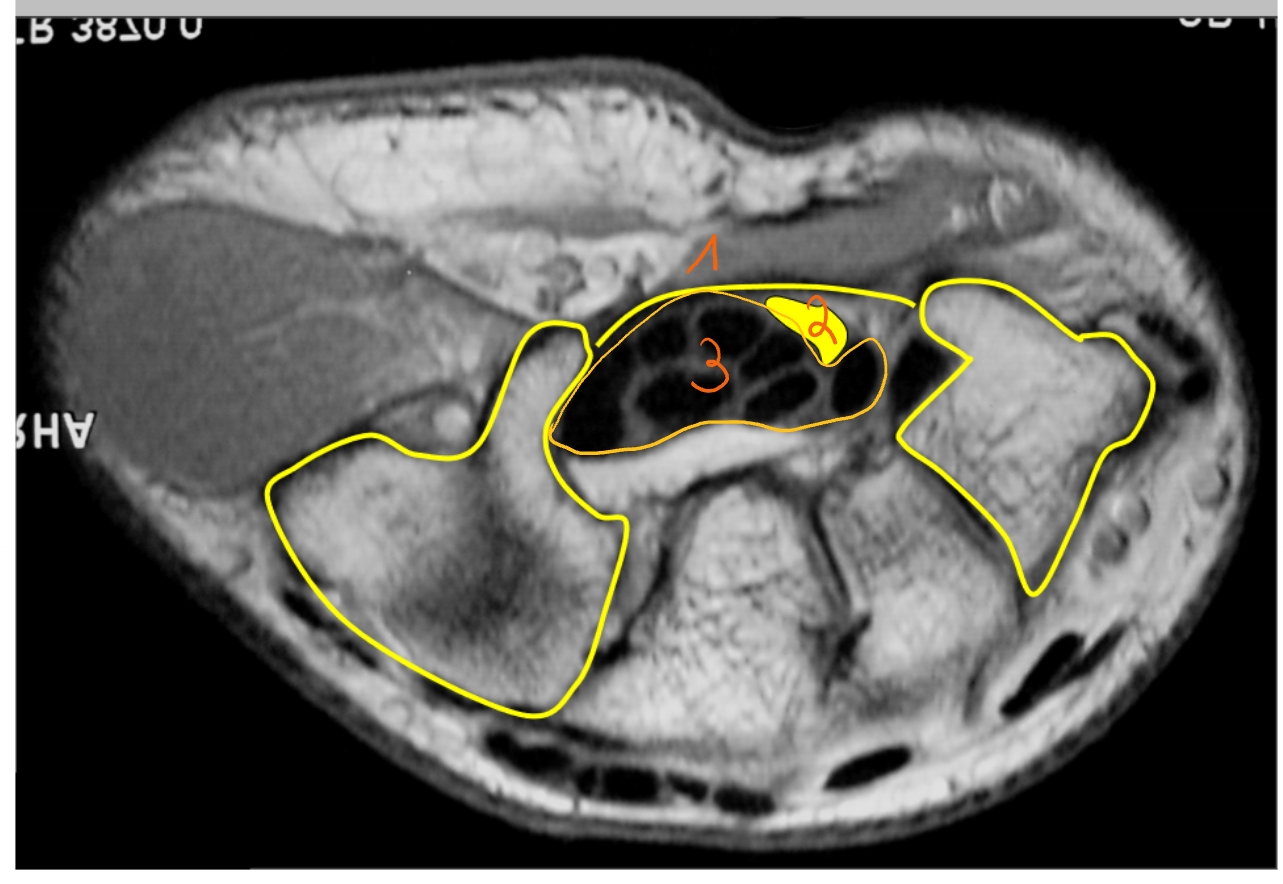

flexor retinaculum

n. medianus

zit in de carpale tunnel

flexorpezen